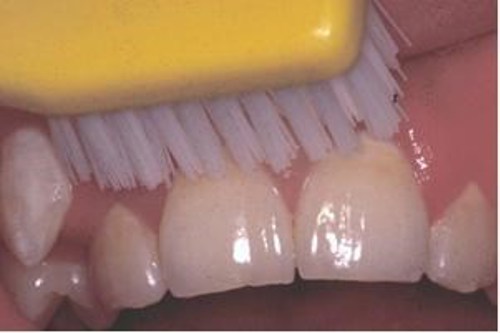

På andet billede vises hvordan man kan standse udviklingen af hullet, hvis man børster grundigt.

- Børste bakterierne væk fra hullet mindst 2 gange om dagen. Læs mere om tandbørstning.